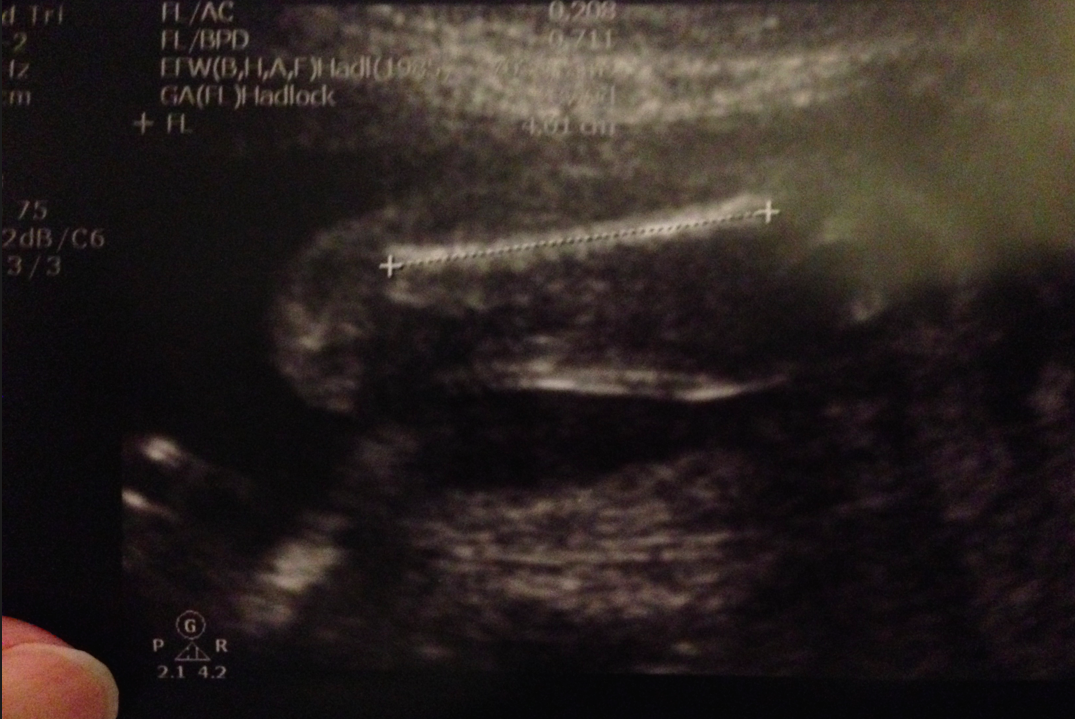

肚腩⋯erhhh?24週size?﹗其實,S醫生話啲parameters係呢啲週數如果正負一星期都屬於完全正常,其實唔駛擔心,不過嘛,得啖笑囉~自從我肚子越來越大之後,day個肚腩都改咗個名叫做邱肚腩,莫非BB呱都有邱小肚腩?﹗:p記得乖乖地,唔好繼續放肆亂咁長肉啦,按步就班,跟時間表生長就最好了﹗知唔知道?

S醫生仲睇咗好多其他部位,有啲睇番相相唔記得咗係乜就唔寫了,記得學咗新嘢,不嬲我都知道要用超聲波做dating的話,即是用超聲波尺寸計番胎兒週數,都係1st trimester時最準,2nd trimester都有多少資訊,再遲就冇意思了,原來量度BB嘅小腦尺寸的話同週數correlate得好好㗎﹗幾多mm就係幾多週,BB呱當然跟番住係23mm啦﹗我哋又數下手指仔腳指仔,係螢光幕上,BB呱繼續「烏蠅手」,郁郁郁郁郁,S醫生都好難捉住佢呢﹗heehee~